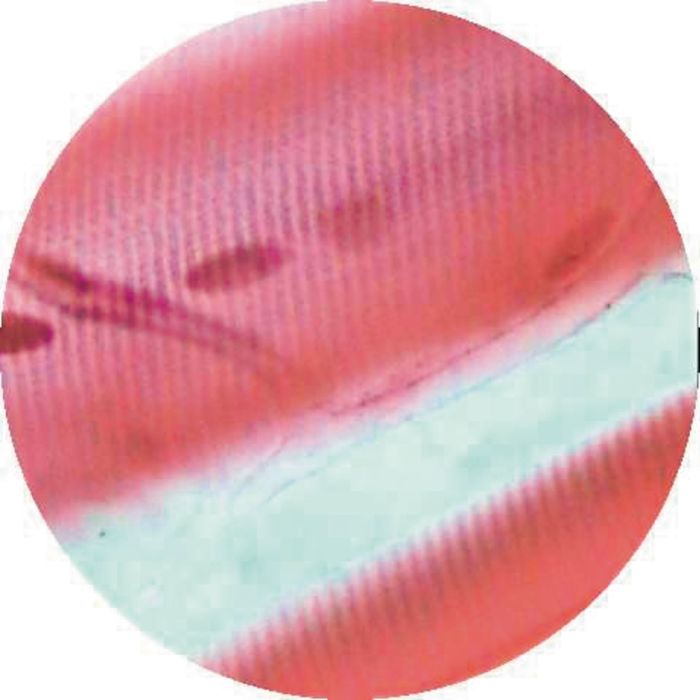

Human cardiac muscle.